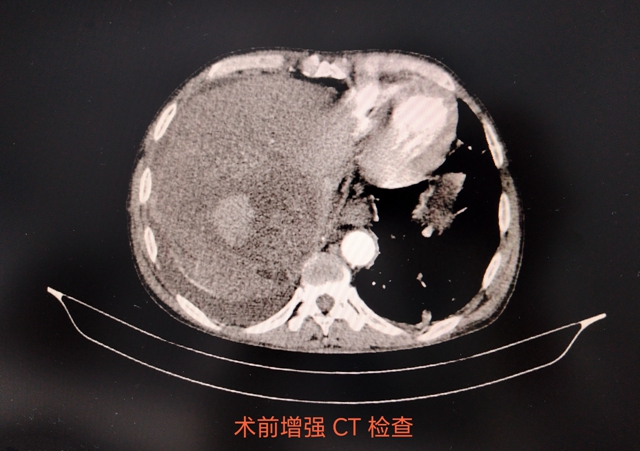

近日,泸州福欣医院成功抢救一名肝癌破裂出血患者。患者中老年男性,四川大学华西医院确诊肝癌,行保守治疗。突发右上腹疼痛入我院,生命体征极度不稳定,影像学提示肝癌伴瘤卒中,肝硬化失代偿、大量腹水,实验室检查提示肝功能衰竭。

经多学科会诊,为抢救生命,决定实施微创介入治疗。由于患者一般情况极差,手术风险极高,同时面临术后肝功能衰竭、全身DIC、多器官功能衰竭等巨大风险,介入手术医生术中如履薄冰,精心设计手术方案、预判风险、反复研判术中可能出现的各种可能并处理预案。在医护人员的努力下,手术顺利完成,术后患者恢复良好,顺利出院。